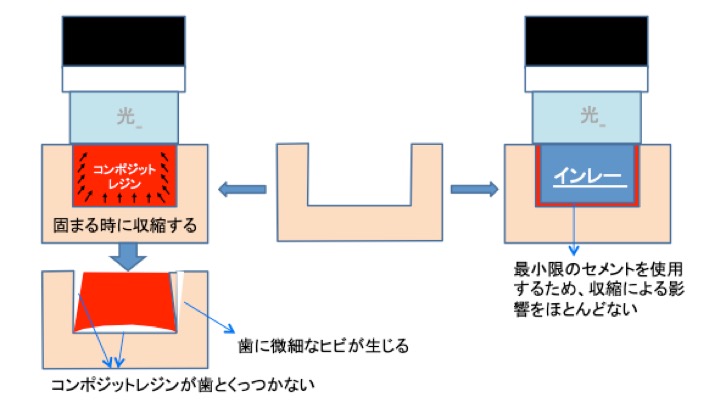

虫歯を削った後、コンポジットレジン(光で固まるプラスチック)で埋めることも可能ですが、虫歯の大きさや場所によっては処置が困難であり、適応でないことがあります。

コンポジットレジンによる虫歯治療は1回で終わりますので、インレーと比較して通院回数が少なくて済みます。ただし、コンポジットレジンにもデメリットがあります。

コンポジットレジンは光をあてると固まりますが、固まる際に収縮します。

虫歯が大きくて詰める量が多い場合、使用するコンポジットレジンの量も多くなるため、収縮量がおおきくなります。

つまり、歯とコンポジットレジンの間に隙間が生じることがあります。そうすると、治療後にしみたり、再治療のリスクが上がったりします。